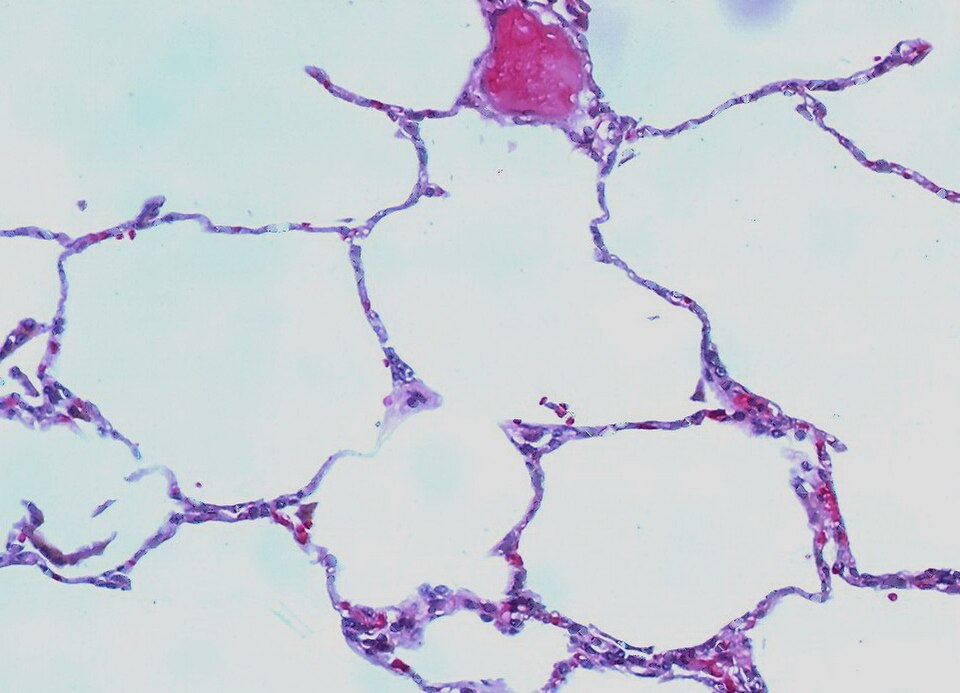

Centrifuged urine sediment showing casts, crystals, and cells